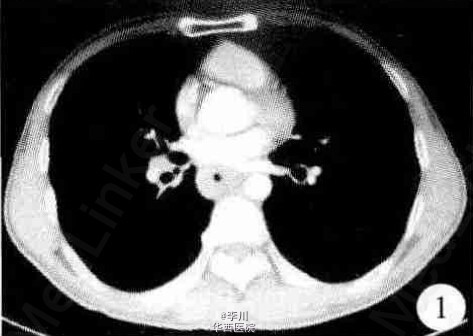

患者, 男, 62 岁。 因进食后胸骨后隐痛 3 个月入院。胸部 CT 示 : 食管中下段管壁增厚 (图 1),考虑食管癌, 纵隔未见肿大淋巴结。食管 X 线钡餐造影示:食管中段管腔充盈缺损, 病变长约 4 cm。电子胃镜检查示:距门齿 31 ~ 35 cm 处食管前壁见一不规则隆起, 表面黏膜糜烂伴有浅溃疡, 质脆易出血。胃镜下取活检见肿瘤细胞呈巢团状弥漫性分布于鳞状上皮下, 考虑为食管癌。行传统左胸后外侧切口手术治疗, 术中探查见肿瘤位于食管中段, 其上缘距主动脉弓下缘约 6 cm, 病变无明显外侵,距离肿瘤上下缘 8 cm 切除病变食管, 清扫区域淋巴结 (主动脉弓下、 隆突下、 食管旁、 下肺韧带、 肺门、 胃左) 共 13 枚一并送检。术毕剖开病变食管观察, 病变大小约 4.0 cm×2.5 cm,肿瘤向腔内呈蘑菇样突起, 边缘与其周围黏膜境界较清楚, 瘤体表面有浅表溃疡。术后病理检查:确诊为食管原发性恶性黑色素瘤。